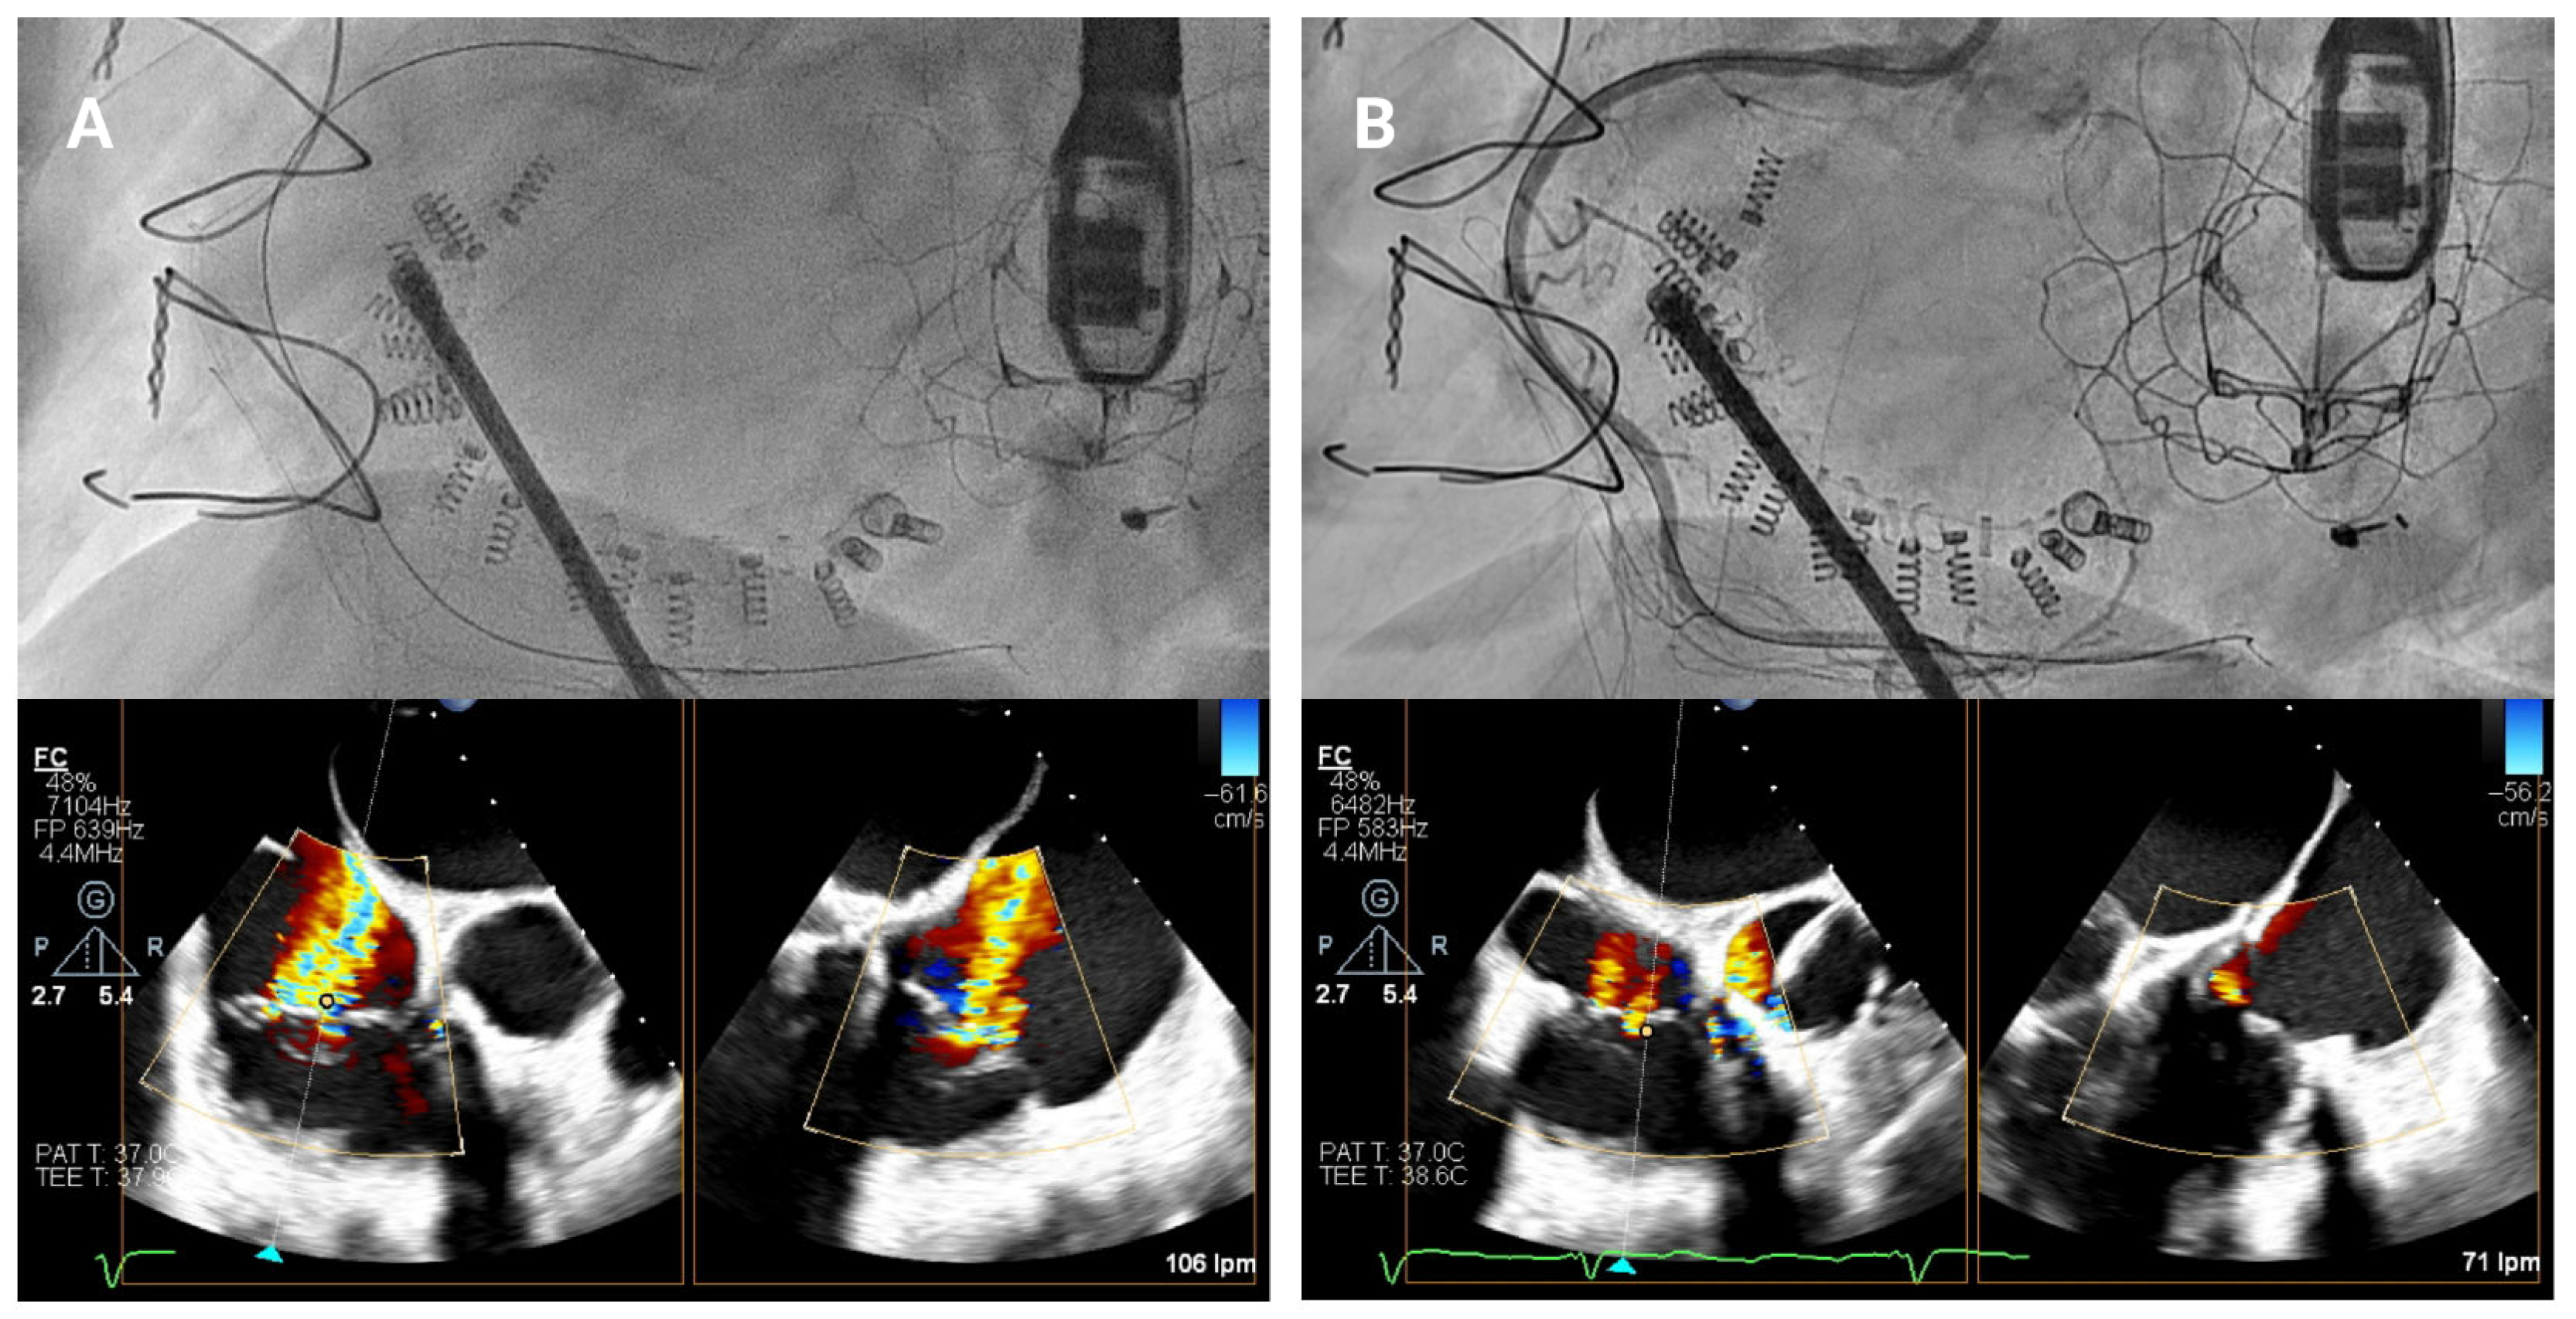

As the guide catheter approaches the tricuspid valve (

Figure 4), it is important to avoid structural interference or leaflet damage. Angiographically, the left anterior oblique projection helps visualize the anteroseptal commissure of the tricuspid annulus and ensures avoidance of the RCA course. Echocardiographically, transgastric views help visualize the anterior and posterior annulus, while high, mid, and deep esophageal views are useful for assessing the lateral annulus.

After the catheter is near the anteroseptal commissure, TEE and angiographic views are used together to check the IC tip alignment as it moves towards the tricuspid annulus. RAO projections allow visualization of the IC’s approach to the annulus with respect to its surrounding anatomy in order to confirm that the catheter’s tip follows the intended trajectory towards the target anchor points and is not obstructed by the leaflet or at risk of inducing injury. TEE bi-plane views are then employed to monitor precise positioning in relation to the hinge points and to ensure that the IC makes accurate contact with the annular tissue.

Figure 4.

Delivery system navigation. The mid-esophageal bicaval view supports real-time visualization of the steerable sheath and guide catheter, while the mid-esophageal short-axis view aids in assessing the distance to the aorta. As the guide catheter nears the tricuspid valve, fluoroscopic left anterior oblique projection helps identifying the anteroseptal commissure and avoiding the right coronary artery.